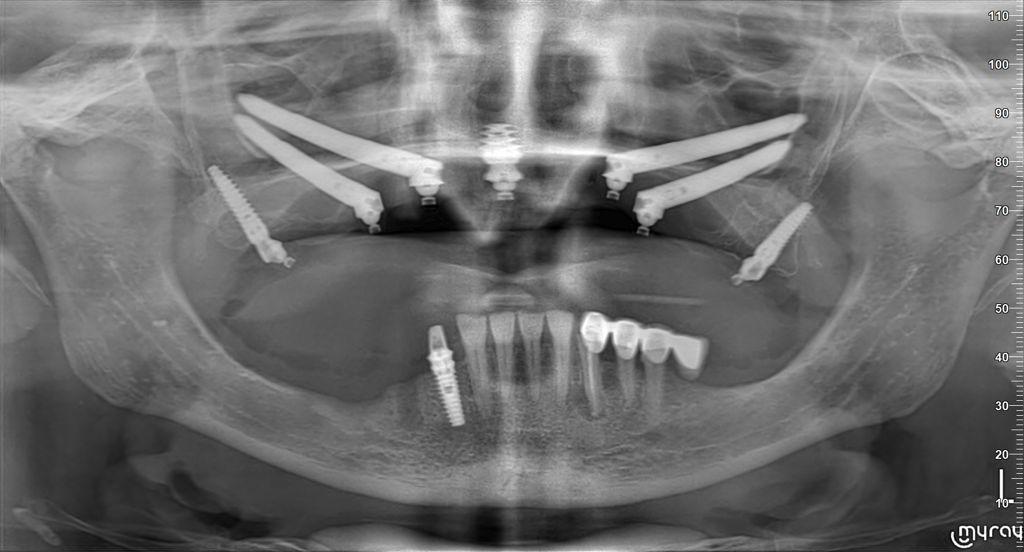

Gli impianti zigomatici sono una soluzione idonea alla riabilitazione di casi complessi con gravissima atrofia del mascellare.

FASE 2 - Studio del repertorio radiologico (Tac – Panoramica – Radiografia) e della stereolitografia